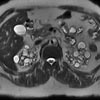

Figure 1 –

This cross-sectional T2-weighted MRI image of the abdomen from the patient's 2006 scan shows bilateral replacement of the kidney parenchyma by cysts of various sizes. No residual kidney tissue is visible.

A recent (2006) MRI scan of the abdomen showed numerous well-defined intraparenchymal and exophytic cysts scattered diffusely throughout both kidneys (Figures 1 and 2). The largest, in the mid-pole of the anterior right kidney, measured 2.9 x 2.8 x 2.9 cm. Compared with the 2002 study, the number of cystic lesions had increased markedly; very little renal parenchyma was visible. Some of these cysts were hemorrhagic; none showed abnormal enhancement.